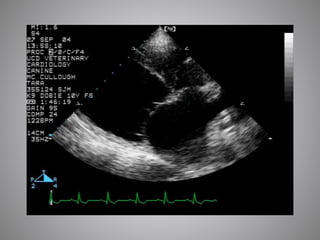

 MMVD: Useful

 Severity, PHT, chordal rupture, LA tear

 DCM:Worse prognosis